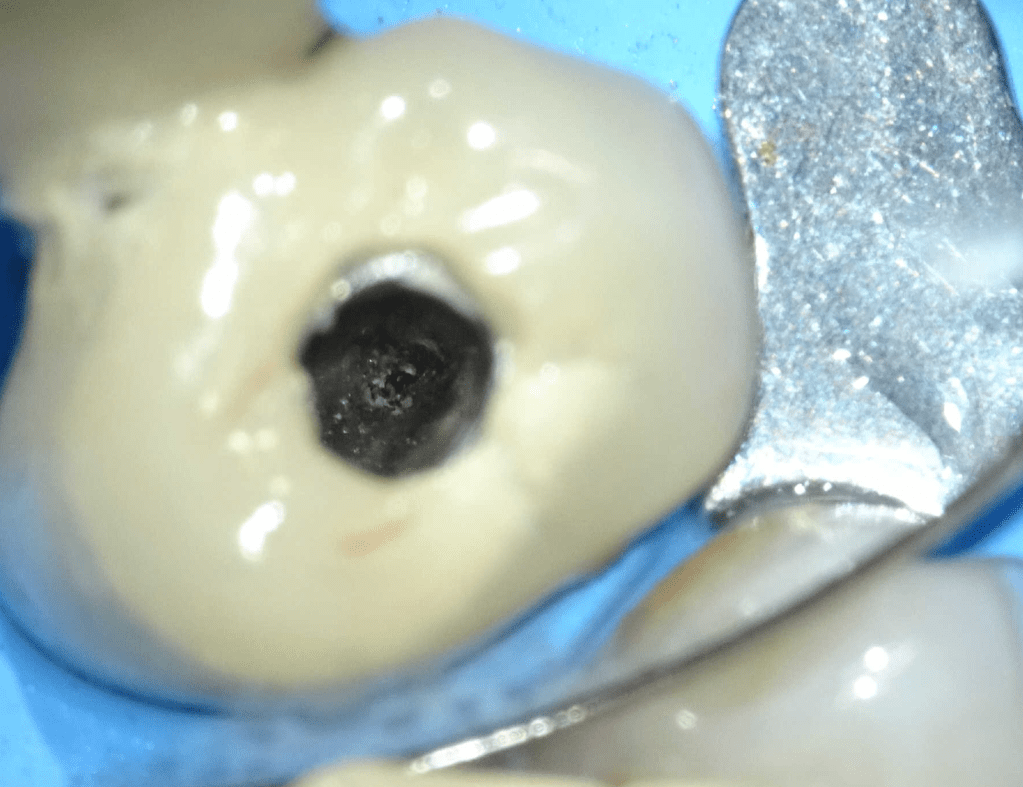

Endodoncias a traves de coronas

20 molar superior a traves de corona

Acceso ultraconservador a través de incrustación reciente